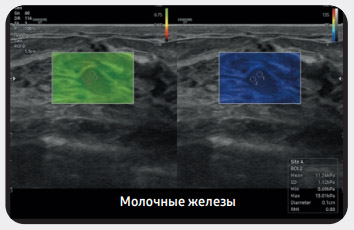

Анализ выбранных участков поражения в молочных железах и составление аналитического отчета

Функция S-Detect™ предназначена для анализа выбранных очагов поражения молочных желез. Отображая данные анализа, она позволяет оптимально организовать диагностику и получить отчет по стандартам BI-RADS ATLAS*.

* Система данных и отчетности по визуализации молочных желез. Atlas — зарегистрированный товарный знак компании ACR. Все права защищены компанией ACR.

Режим S-Shearwave - молочная железа

Режим MV-Flow - узел в молочной железе